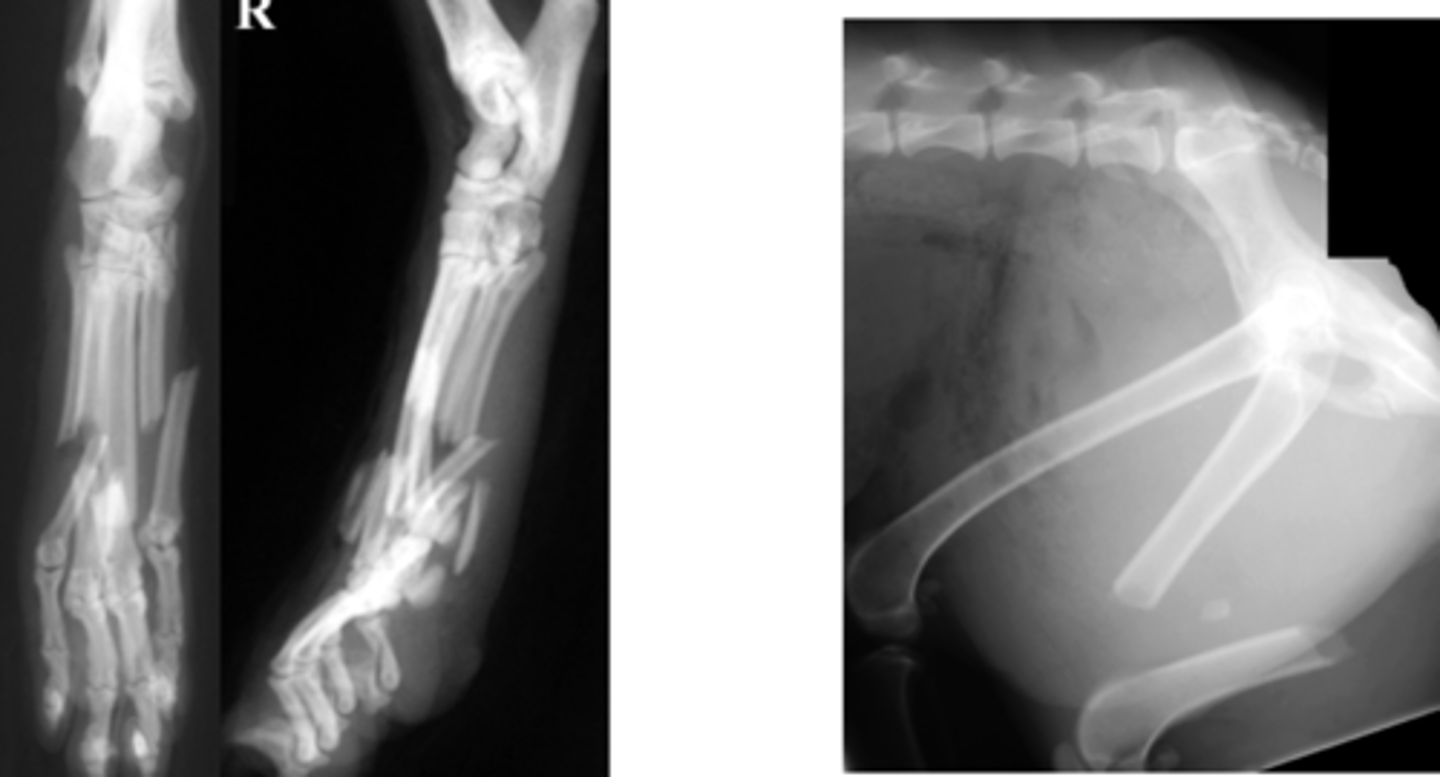

Identify the fracture type?

Spiral

What kind of stress will cause a spiral fracture?

Slow twisting injury